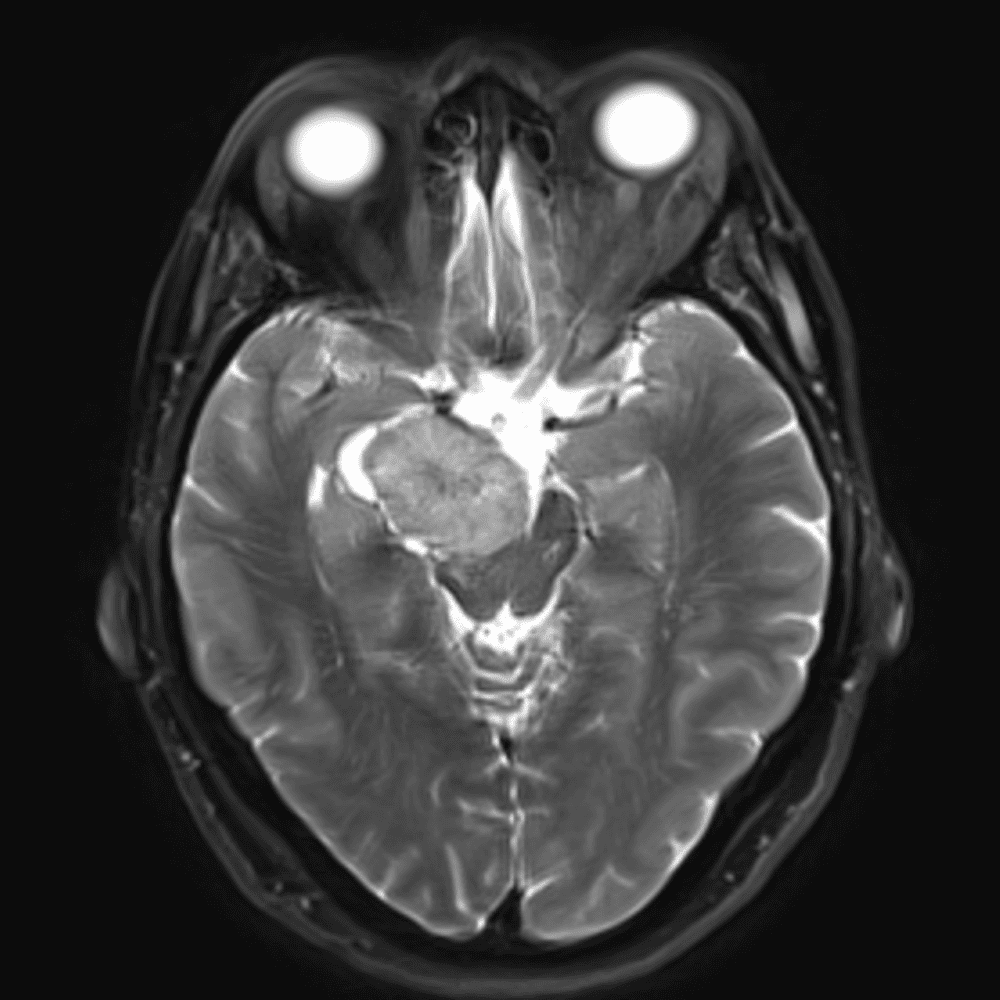

๋‹น์ง ์‹œ ํ”ํžˆ ๋ณผ ์ˆ˜ ์žˆ๋Š” ์‚ฌ๋ก€์˜ ์ „ํ˜•์ ์ธ ์˜ˆ๋ฅผ ํฌํ•จํ•ฉ๋‹ˆ๋‹ค.

39 ์‚ฌ๋ก€

์—ฐ์Šต

๋ฏธ๋ฌ˜ํ•˜๊ฑฐ๋‚˜ ์–ด๋ ค์šด ์‚ฌ๋ก€์™€ ์ผ๋ถ€ ์ •์ƒ ์‚ฌ๋ก€๋ฅผ ํฌํ•จํ•˜์—ฌ ๋‹น์ง์„ ์‹œ๋ฎฌ๋ ˆ์ด์…˜ํ•ฉ๋‹ˆ๋‹ค.

50 ์‚ฌ๋ก€